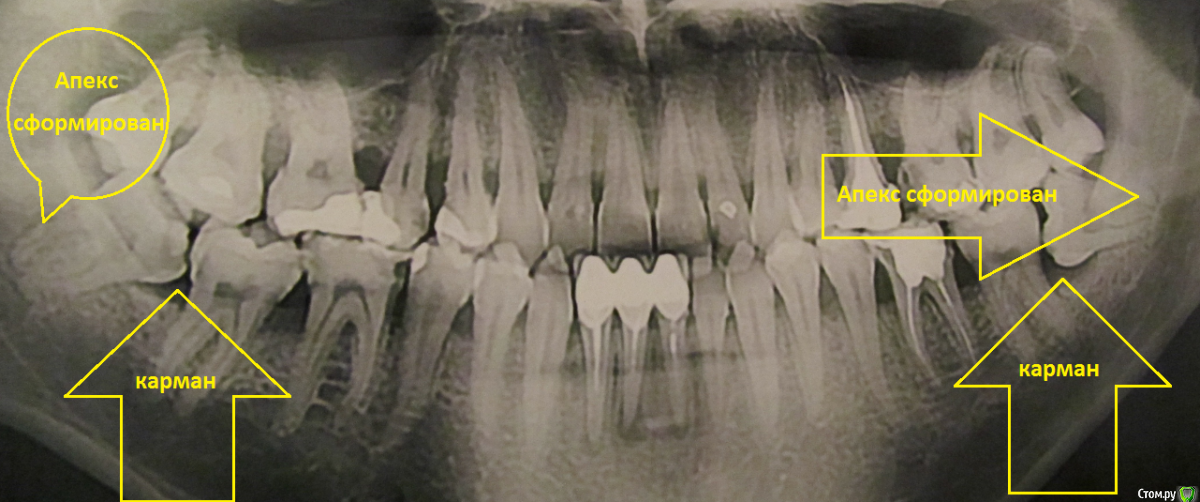

paradontit Опубликовано 12 ноября, 2016 Поделиться Опубликовано 12 ноября, 2016 Снимок в 2013 годуСнимок в этом году, лечения не было никакогоДорогие парадонтологи, посоветуйте метод лечегия в данной ситуации. Очень интересуют независимые мнения. Ссылка на комментарий

___49___ Опубликовано 14 ноября, 2016 Поделиться Опубликовано 14 ноября, 2016 Ваши нижние 8 ки не встанут в правильную позицию, неверное положение с упором в соседние зубы + их основной рост уже прекратился, между 8ками и 7ками сформирован карман который не возможно прочистить (принцип бутылки) - это приводит к возникновению кариеса (47 зуб уже необходимо осматривать по дистальной стенке ) или воспалению . Удаляйте. 1 Ссылка на комментарий

St. Опубликовано 14 ноября, 2016 Поделиться Опубликовано 14 ноября, 2016 Плюс к выше описанным рекомендациям обратите внимание на нижние центральные зубы под коронками. На них идет хроническое воспаление на корнях вследствие не идеально пролеченых каналов 2 Ссылка на комментарий

St. Опубликовано 15 ноября, 2016 Поделиться Опубликовано 15 ноября, 2016 Я, к сожалению, не узнал, в каких зубах у меня залипухи (кроме зубов под коронкой). На первый взгляд, как минимум эти. Ссылка на комментарий

St. Опубликовано 15 ноября, 2016 Поделиться Опубликовано 15 ноября, 2016 Снять камень - это само собой, но применим ли здесь Вектор или какой нужен кюретаж - не ясно. Лучше кюретаж (какой контретно можно решить только после очного осмотра ) 2 Ссылка на комментарий